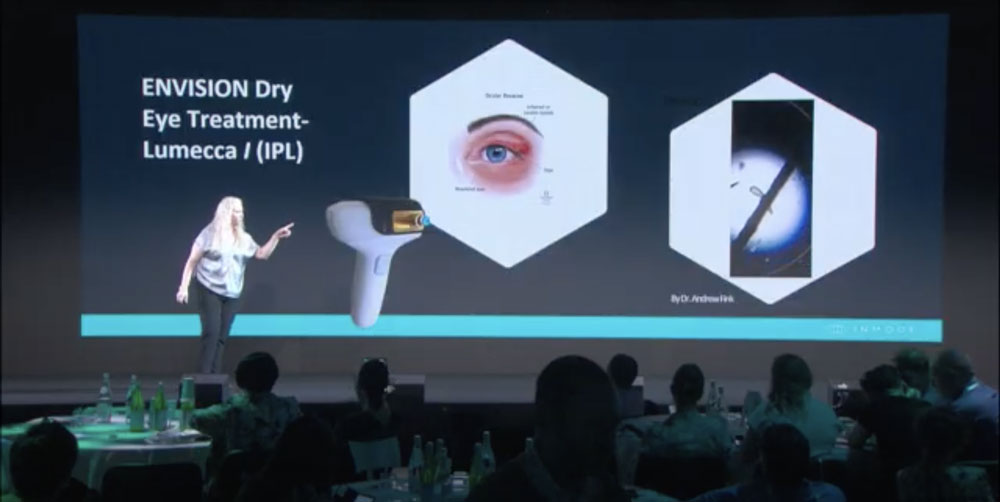

Non-surgical Dry Eye Treatment

Dr. Elvira Gur Lautman explains how Envision’s Forma-I and Lumecca-I address meibomian gland dysfunction with RF and IPL solutions.